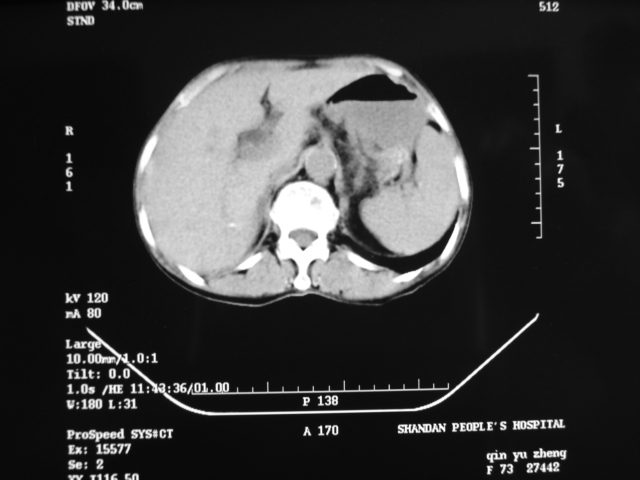

同事奶奶,73岁,腹痛一年,夜晚较重,潜血+++,拒绝增强,考虑左肾ca并腹膜后转移;请各位老师帮忙看看,谢谢!

左肾癌侵及输尿管上段,腹膜后多发淋巴结转移,脾脏钙化灶。至于潜血+++,要考虑消化道病变,本次ct片肠腔未见明显异常。

1)考虑左肾癌侵犯肾盂并腹膜后淋巴结转移。2)脾脏钙化灶。

考虑左肾癌侵犯肾盂并腹膜后淋巴结转移。